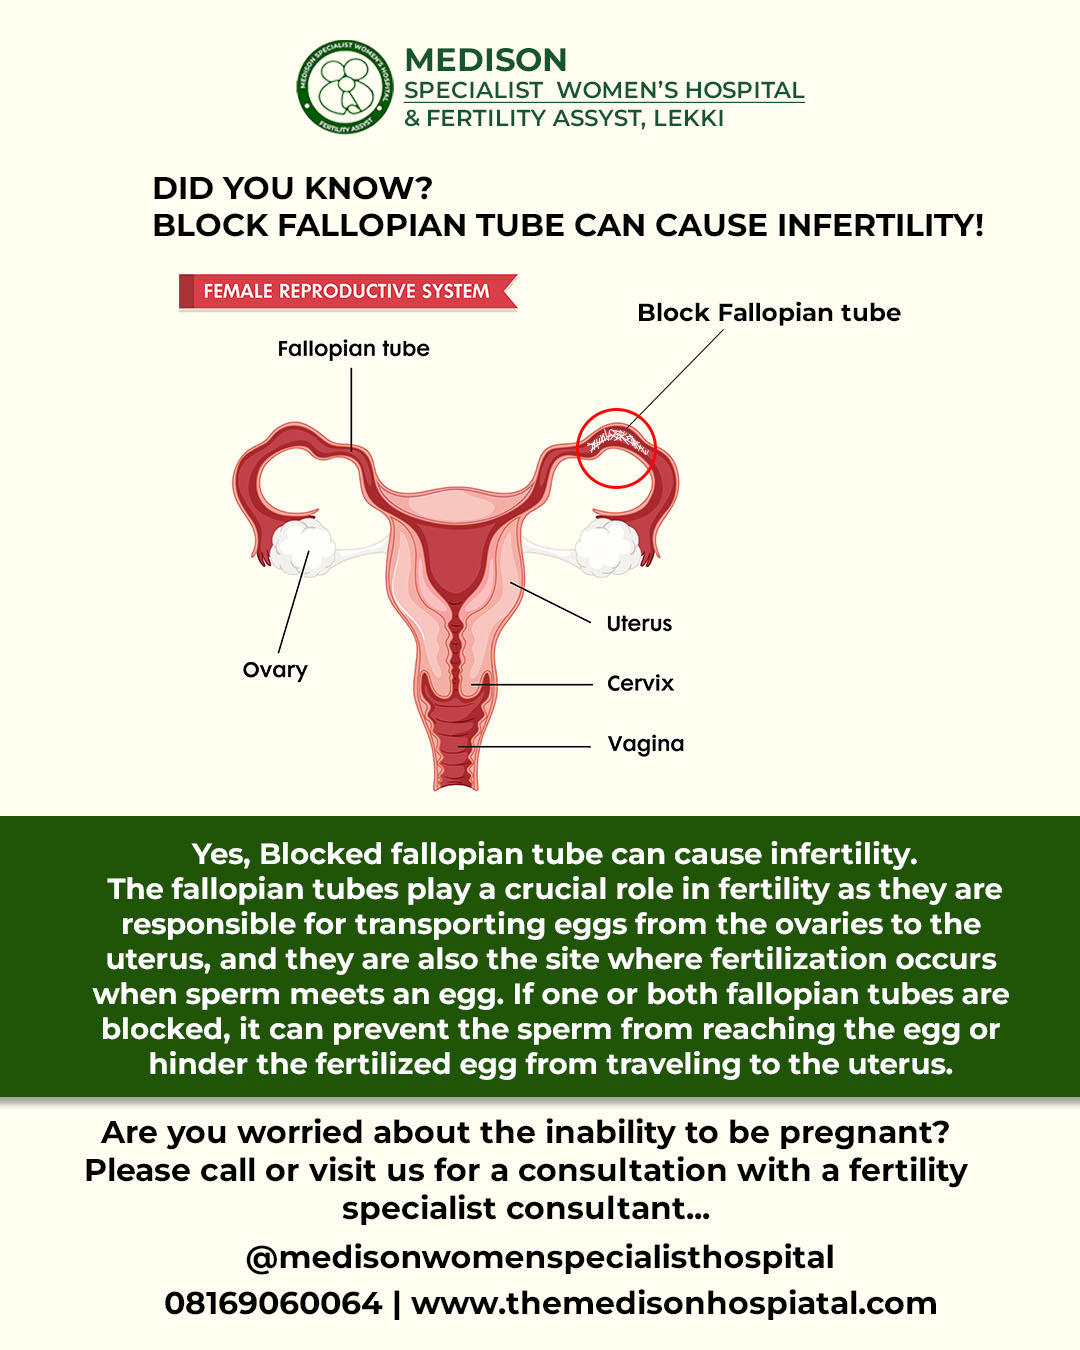

Tubal Blockage Causes Symptoms Treatments Our Approach

Blocked Fallopian Tubes Treatment In Ludhiana Punjab Likhi Test Tube

Fallopian Tube Blockage

Fallopian Tube Blockage

Blocked Fallopian Tubes Treatment In Ludhiana Punjab Likhi Test Tube